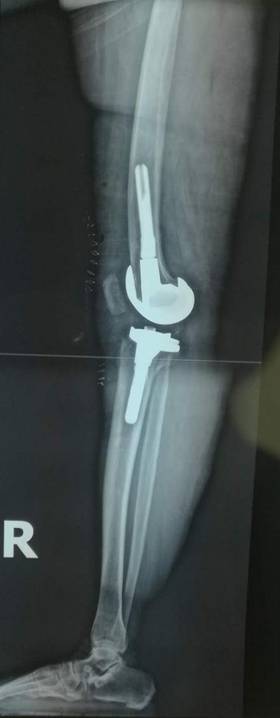

术前术后对比

全膝关节翻修术

全髋关节翻修术